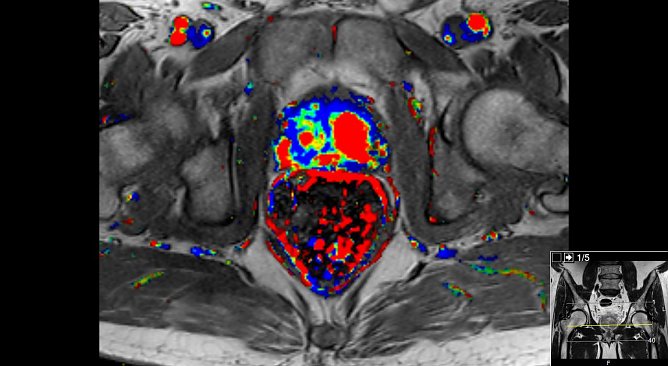

Prostata-Karzinom (Foto: Südharz Klinikum)

Tumorbeispielbild im MRT in der Dynamik und der ADC-MessungDie dortigen Urologen unter Leitung von Prof. Stolzenburg lassen bereits seit einigen Monaten die diagnostischen MRT-Untersuchungen der Prostata ihrer Patienten am hochmodernen 3T-MRT in Nordhausen durchführen.